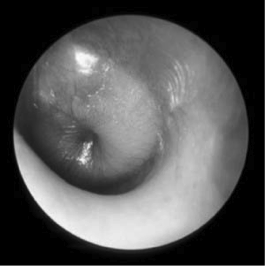

Causative agent?

Pneumococcus

(this is bulging TM in otitis media)